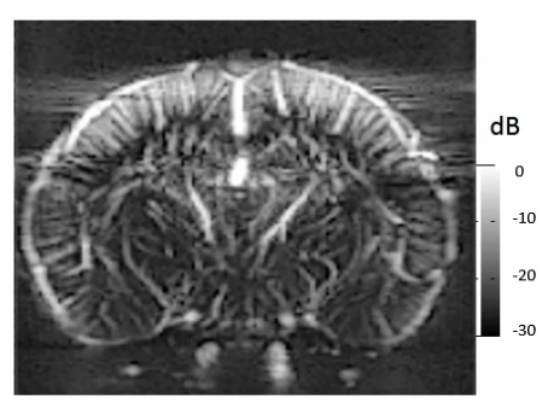

fUS是一种支持动物实时脑功能成像的新方法,相关方法与应用研究已有近40篇论文发表于Nature、Nature子刊、Science子刊、Cell、PNAS、Neuron等高水平期刊。fUS有望在神经科学基础研究、药理学与药物研发、中风与神经血管成像等领域发挥重要作用。

Iconeus One 是世界首款基于功能性超声技术(fUS,functional ultrasound)设计的成像系统,支持自由活动动物脑功能实时成像及血流成像。

Iconeus One系统搭载多种专用成像探头,可对清醒或自由活动状态的小鼠、大鼠以及非人灵长类等动物进行全脑实时动态功能成像及血流成像、器官组织的结构及血流成像。可兼容电生理记录与光遗传学。时间分辨率10 ms,普通模式空间分辨率100 μm,超高分辨率模式空间分辨率10 μm。